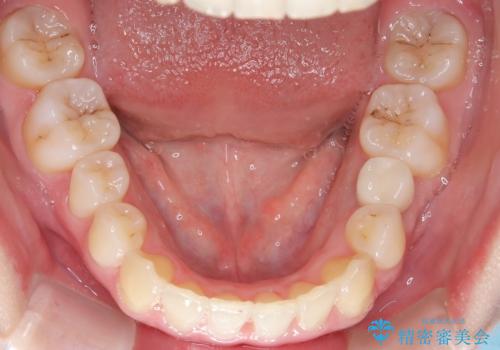

左下5番は先天性欠損のため乳歯は抜歯しインプラントにて欠損補綴しています。